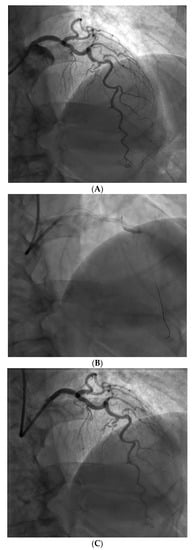

Figure 3.

Example of a complex lesion involving the LAD in a patient with angina and severe tortuosity (A). Despite the tortuosity, the lesion was successfully wired, ballooned, and stented robotically (B). Post stent result shown in (C).